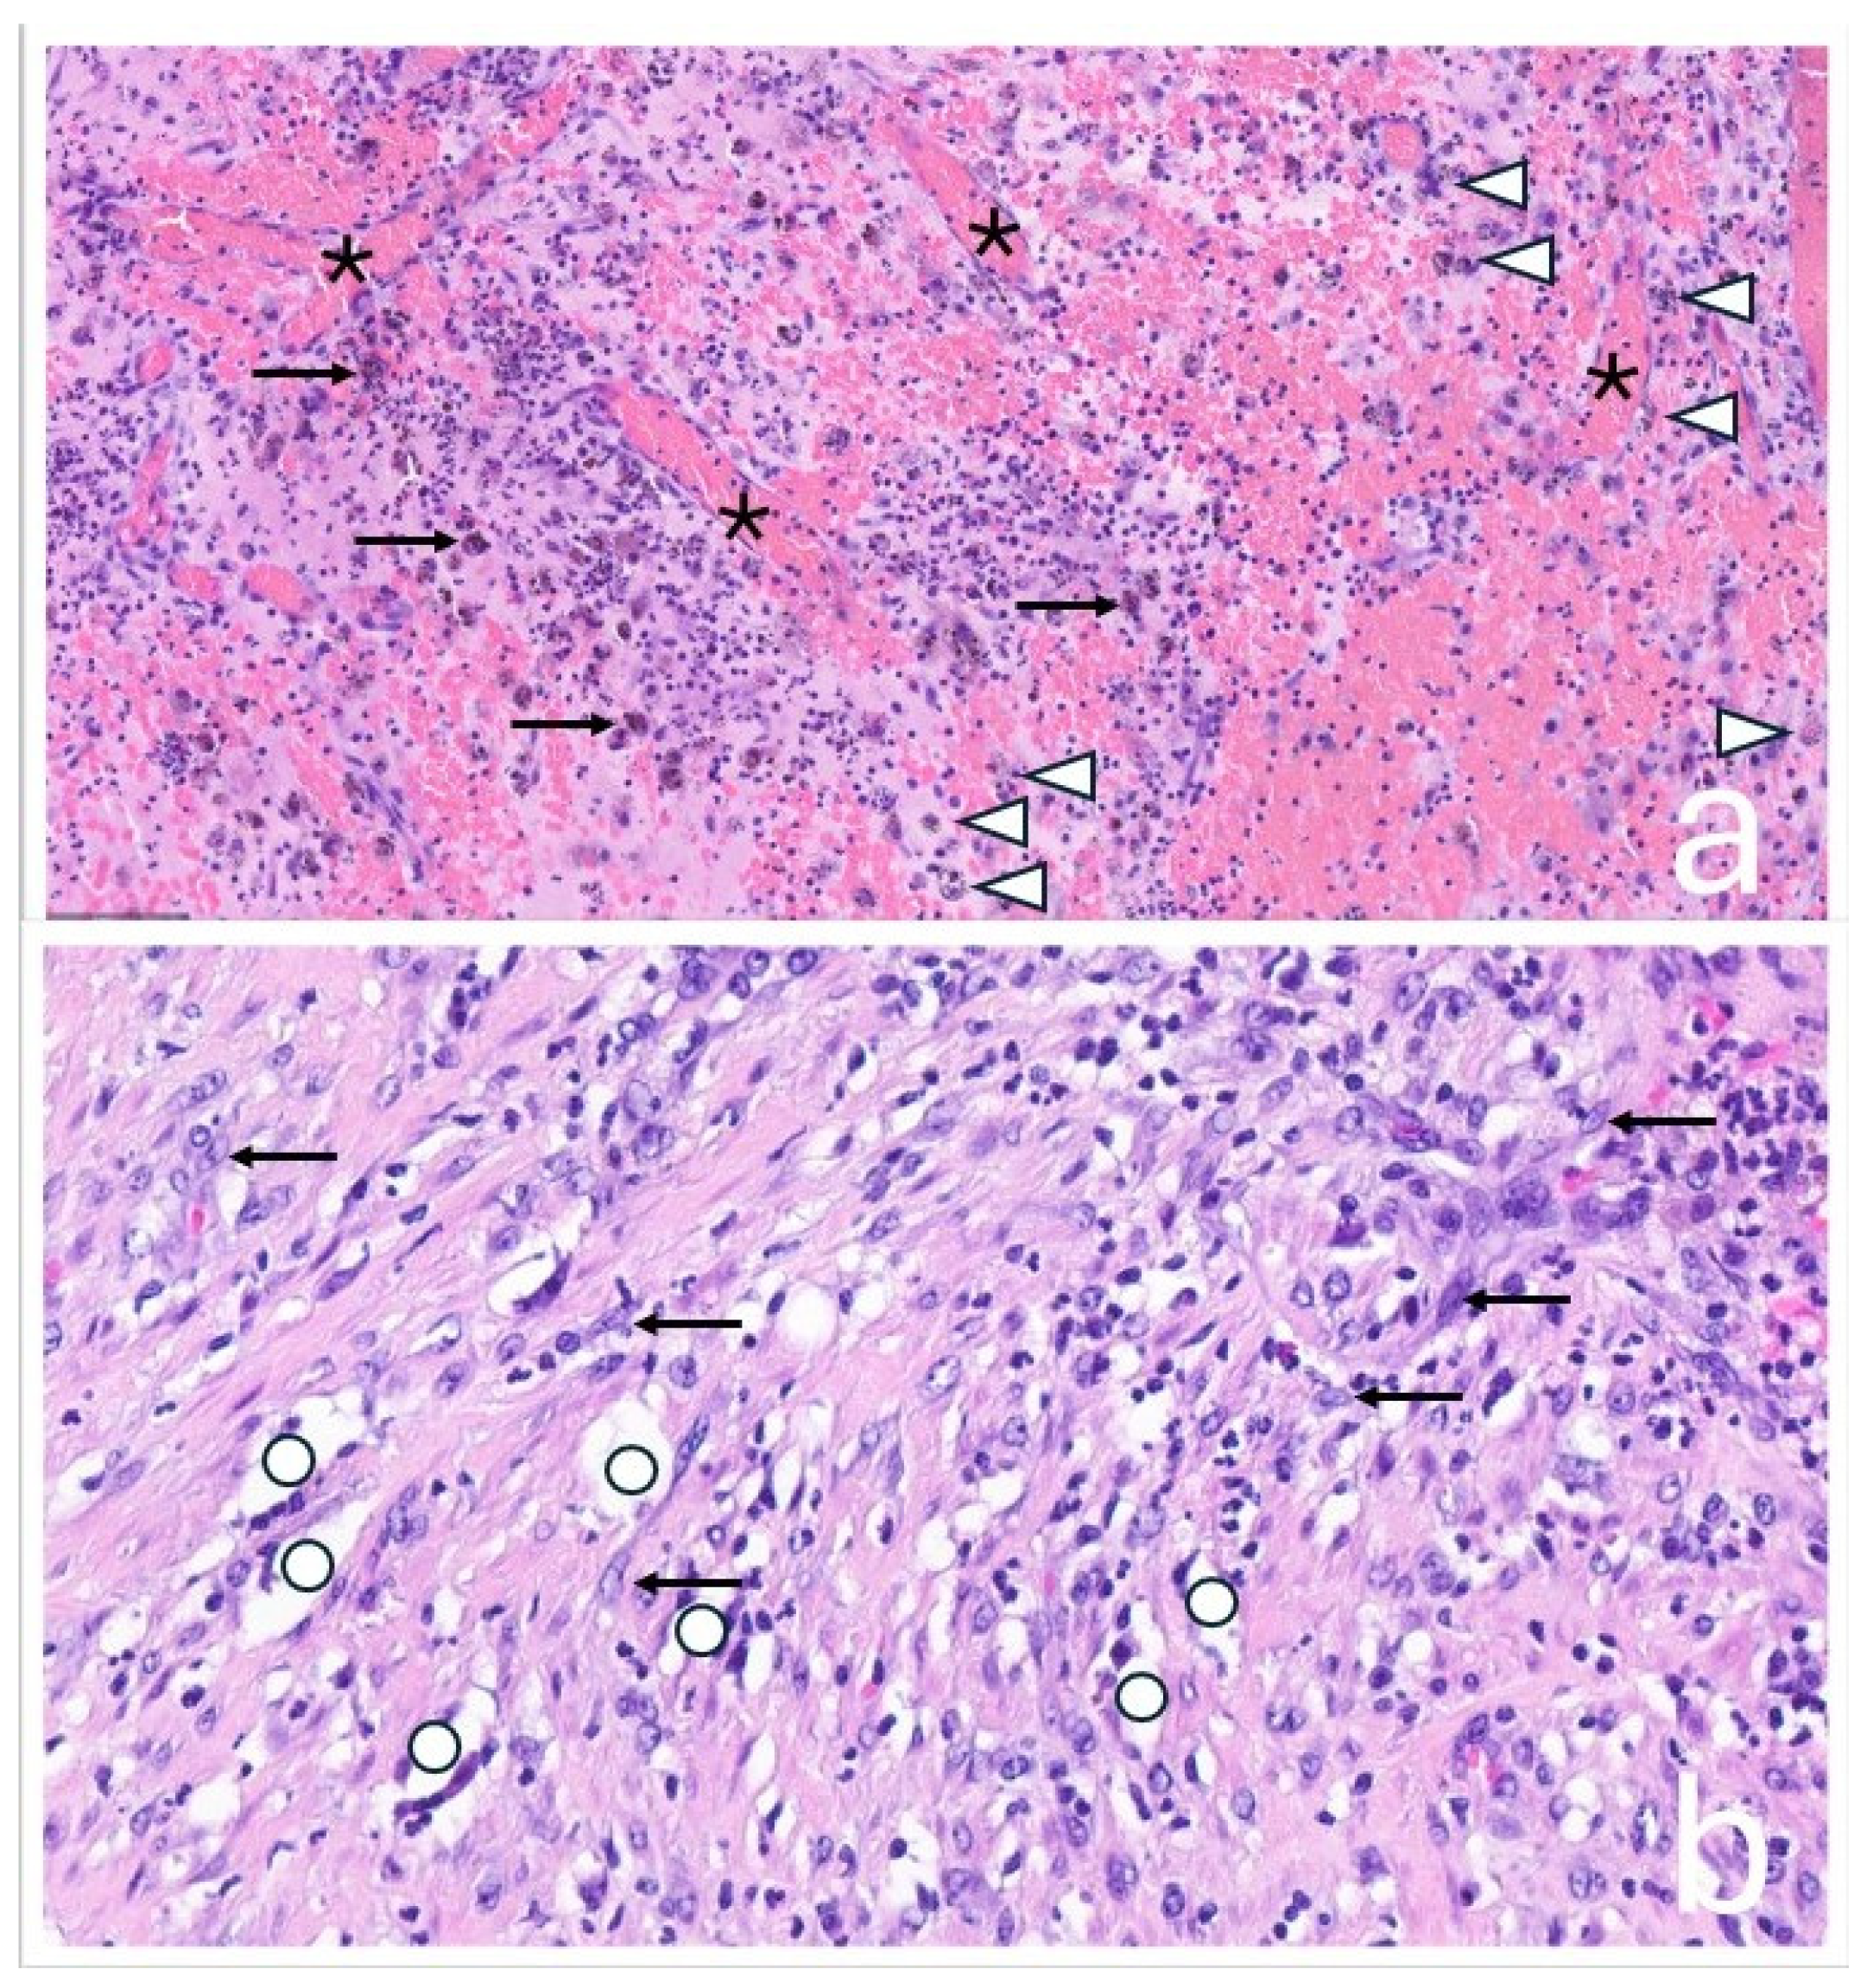

At the time of orthopedic examination, the hip joint was functional and non-painful. However, by reconstructing additional imaging planes from the existing CT and MRI datasets, the close anatomical relationship between the hip joint and the tumor mass could be visualized more clearly. (Figure 4).

Figure 4. Additional reconstructed CT (a) and MRI (b) images demonstrate the close anatomical relationship between the pelvic mass (+) and the distally located total hip arthroplasty (*). The red and blue lines in the cross-sectional images indicate additional calculated planes that show the spatial proximity between the implant and the mass.